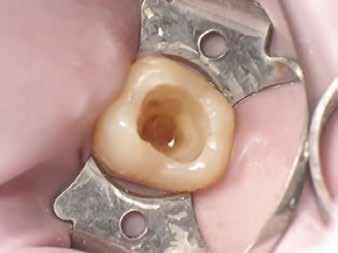

A fogat 37%-os foszforsavval kondícionálta, majd egy 4. generációs dentin bondot (Optibond FL, Kerr) alkalmazott. A II. osztályú dobozt először centripetálisan zárta [19], folyékony és melegített kompozit kombinációjával, szekciós matrica segítségével.

A dentint hiperkróm, közepes opacitású pasztakompozittal modellezte, amely optikai tulajdonságaiban utánozza a természetes dentint (14. ábra). A barázdarendszerbe okker árnyalatú színezőanyagot vitt fel a restauráció színintenzitásának fokozása érdekében (15. ábra).

Ezután közepes transzlucenciájú, zománcszínű kompozitot helyezett a kavitásba, az okkluzális iránytű technika alkalmazásával. Külsőleg sötétbarna színezést vitt fel a barázdák elszíneződésének imitálására (16. ábra).

A restauráció polírozását korongok és szilikonpolírozók kombinációjával végezte, majd az okklúzió ellenőrzését követően a pácienst a rendelőből otthonába bocsátották. Megjegyzendő, hogy a finírozást követően az eredeti okkluzális anatómia csak minimális mértékben módosult (17. ábra).